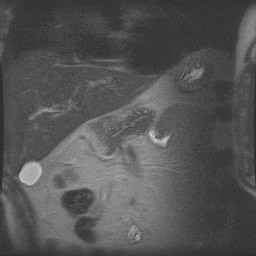

Abdomen